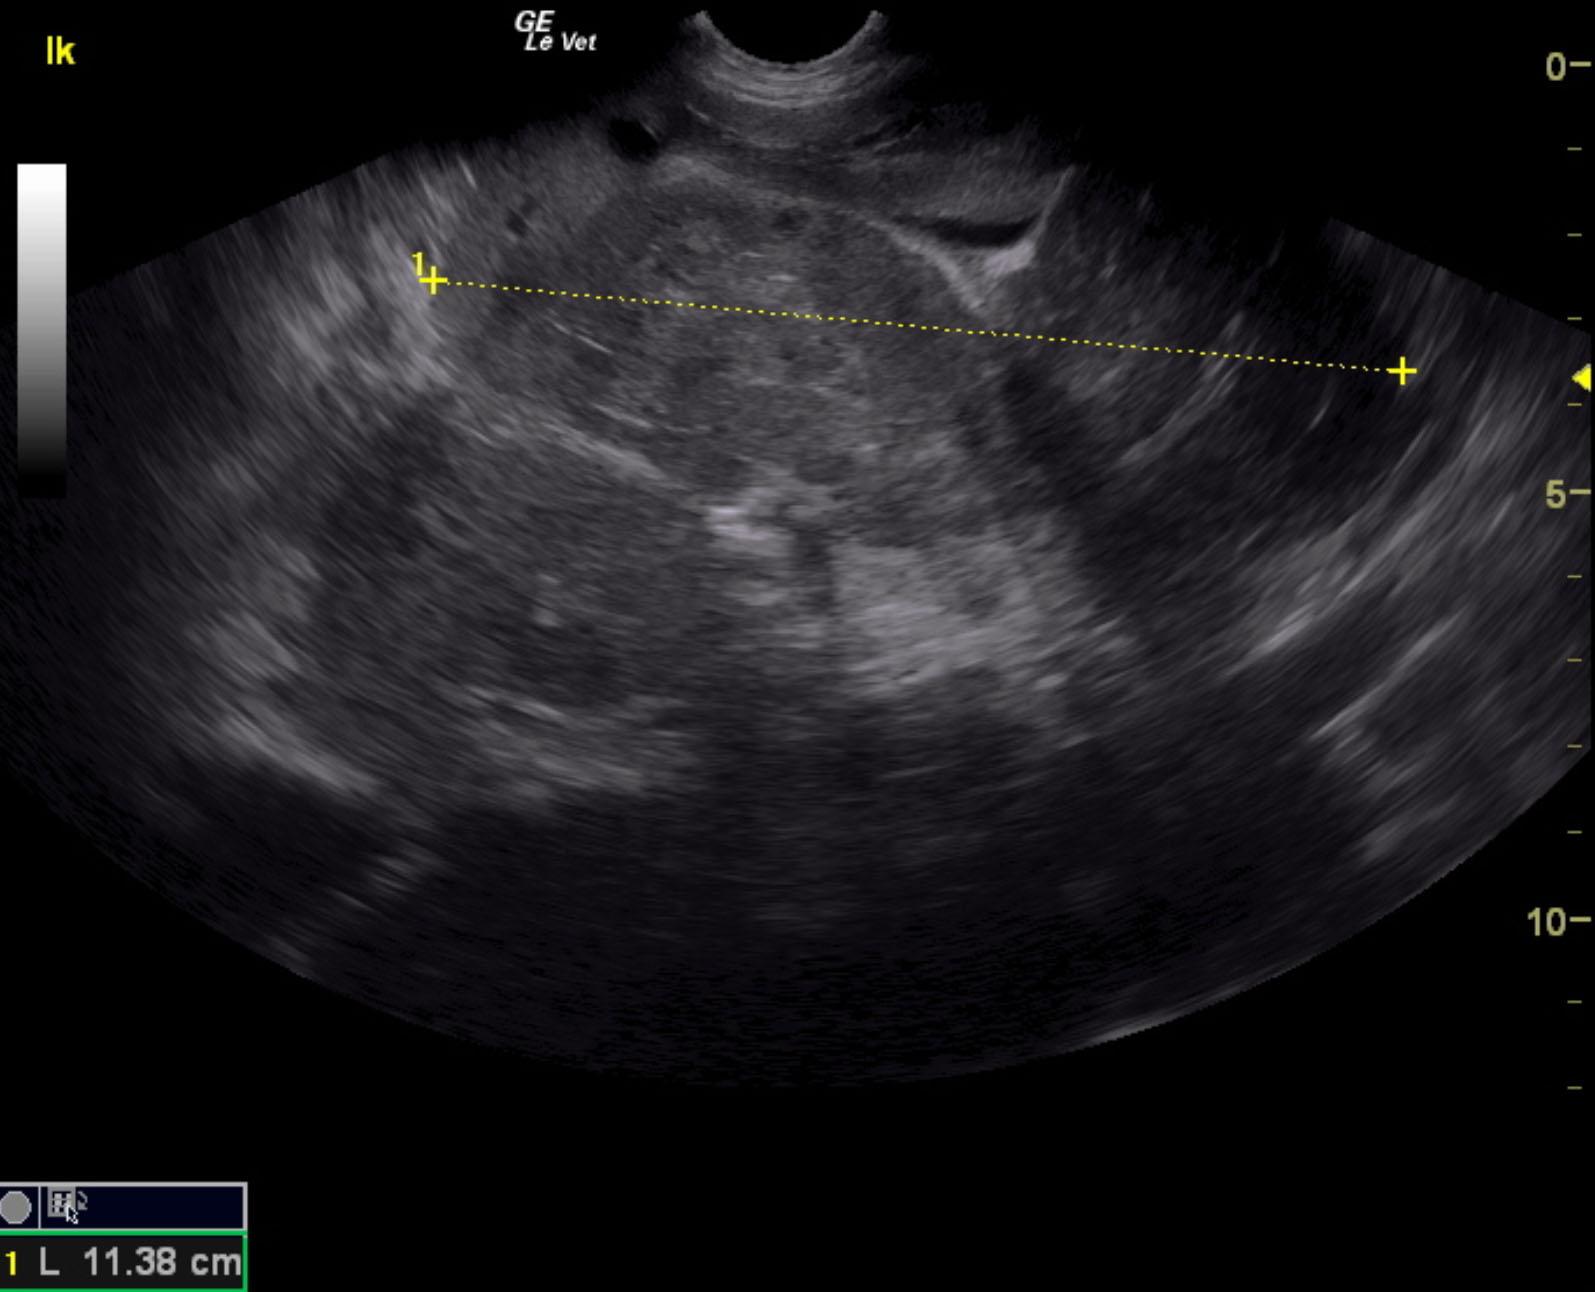

A 7-year-old FS mixed breed dog was presented for evaluation of weight loss and PU/PD. Abnormalities on blood work were neutrophilia, mild hypoglycemia (49), hyperglobulinemia, and elevated cobalamine.